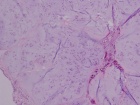

59 year old male c/o left calf swelling

Zoom image: Cell stain Cell stain.